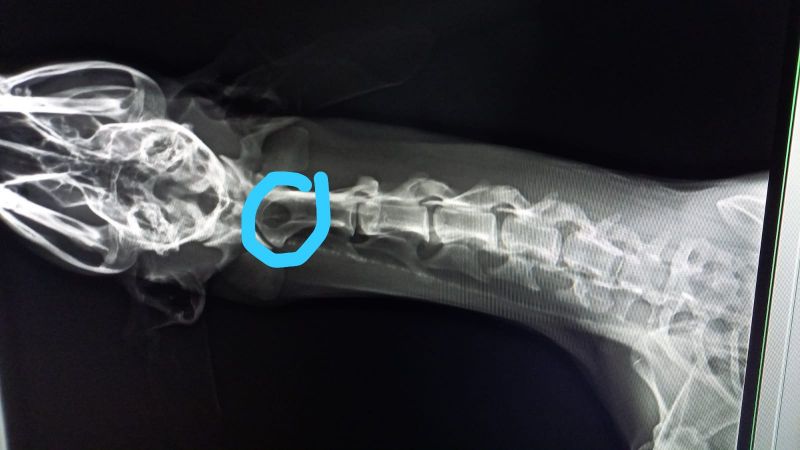

Pilar hat Esperanza bereits zu zwei Tierärzten in Zaragoza gebracht. Die Galga läuft seltsam und schrie regelrecht vor Schmerzen, insbesondere wenn sie am Hals angefasst wird. Es ist schrecklich, die arme Galga so leiden zu hören. Leider wissen wir aktuell noch nicht, was Esperanza hat. Beide Tierärzte haben unterschiedliche Vermutungen - es könnte eine alte Verletzung, aber auch ein Tumor an den Halswirbeln sein. Genauers kann nur ein MRT zeigen, welches auch in Spanien sehr kostenintensiv ist.

Update 14.07.: Nach diversen Untersuchungen und einer Nacht in der Tierklinik schließen die Tierärzte sowohl einen Tumor als auch einen Bandscheibenvorfall aus. Sie wollen aber noch die zerebrospinale Flüssigkeit untersuchen die sie schon, als Esperanza in Narkose war, abgenommen haben. Wir hoffen dass bald eine Diagnose gestellt werden und der süßen Maus geholfen werden kann.